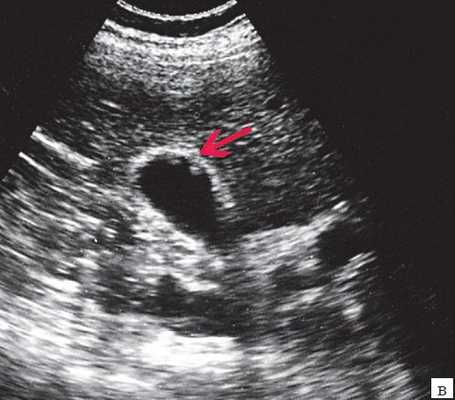

Рис. 1. Ультразвуковая картина билиарной гипертензии при механической желтухе.

а) Расширенные внутрипеченочные протоки.

б) Увеличенный желчный пузырь с густой взвесью (красная стрелка) и расширенный ОЖП (синяя стрелка).